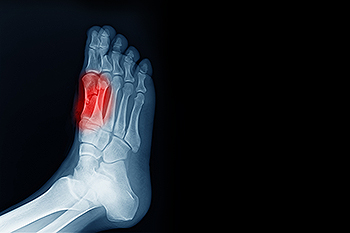

Broken toes can range from simple cracks in the bone to more severe fractures that involve joint displacement or multiple bone fragments. These injuries often result from sudden trauma, such as dropping a heavy object on the foot or forcefully striking a hard surface. Common symptoms include sharp pain, swelling, bruising, and difficulty walking, especially if pressure on the affected toe causes discomfort. A toe that appears crooked or shortened compared to its neighbors may indicate a displaced fracture or dislocation. A podiatrist will typically perform a thorough foot exam and may use X-rays to confirm the type and severity of the fracture. If the bone is misaligned or severely broken, surgery may be needed to restore proper toe position and prevent long-term complications. If you have broken a toe, it is suggested that you make an appointment with a podiatrist for an exam and suggested treatment options.

What to Know About a Broken Toe

Although most people try to avoid foot trauma such as banging, stubbing, or dropping heavy objects on their feet, the unfortunate fact is that it is a common occurrence. Given the fact that toes are positioned in front of the feet, they typically sustain the brunt of such trauma. When trauma occurs to a toe, the result can be a painful break (fracture).